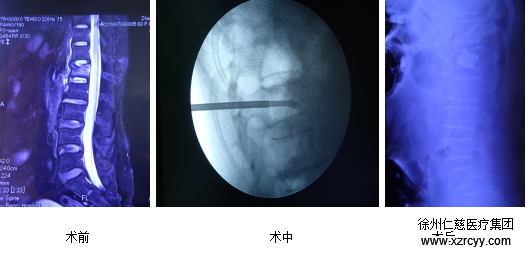

微創(chuàng)椎體成形術(shù)治療老年性骨質(zhì)疏松性脊椎骨折 第二天即可下床

7月12日上午,在徐州仁慈醫(yī)院骨科病房,剛做完微創(chuàng)脊柱椎體成形術(shù)兩天的郝奶奶正在過道活動。郝奶奶的主治醫(yī)生張冶說,郝奶奶恢復(fù)得這么快,是因?yàn)獒t(yī)院的骨科團(tuán)隊(duì)為她制定了私人治療方案——微創(chuàng)脊柱椎體成形術(shù)。

張冶醫(yī)生在給郝奶奶手術(shù)中

在了解了郝奶奶的傷情后,仁慈骨科團(tuán)隊(duì)建議手術(shù)治療,并為其制定了私人的治療方案。 在傷后第三天仁慈骨科醫(yī)生為郝奶奶做了微創(chuàng)脊柱椎體成形術(shù),術(shù)后患者疼痛消失,第二天即下床活動,治療效果良好。

隨著微創(chuàng)技術(shù)和手術(shù)器械的發(fā)展,對骨質(zhì)疏松性脊椎壓縮性骨折或引起明顯后凸畸形者,如患者一般情況及各項(xiàng)檢查良好,可考慮行椎體成形術(shù)。椎體后凸成形術(shù)是一種微創(chuàng)治療脊柱骨質(zhì)疏松性骨質(zhì)的先進(jìn)技術(shù),手術(shù)將一個套管插入椎體,然后插入一個擴(kuò)張器,使用這種擴(kuò)張器使壓縮的椎體復(fù)位并恢復(fù)椎體原來的高度,在椎體內(nèi)形成一個空腔可以填充骨水泥,達(dá)到骨質(zhì)強(qiáng)化的作用。